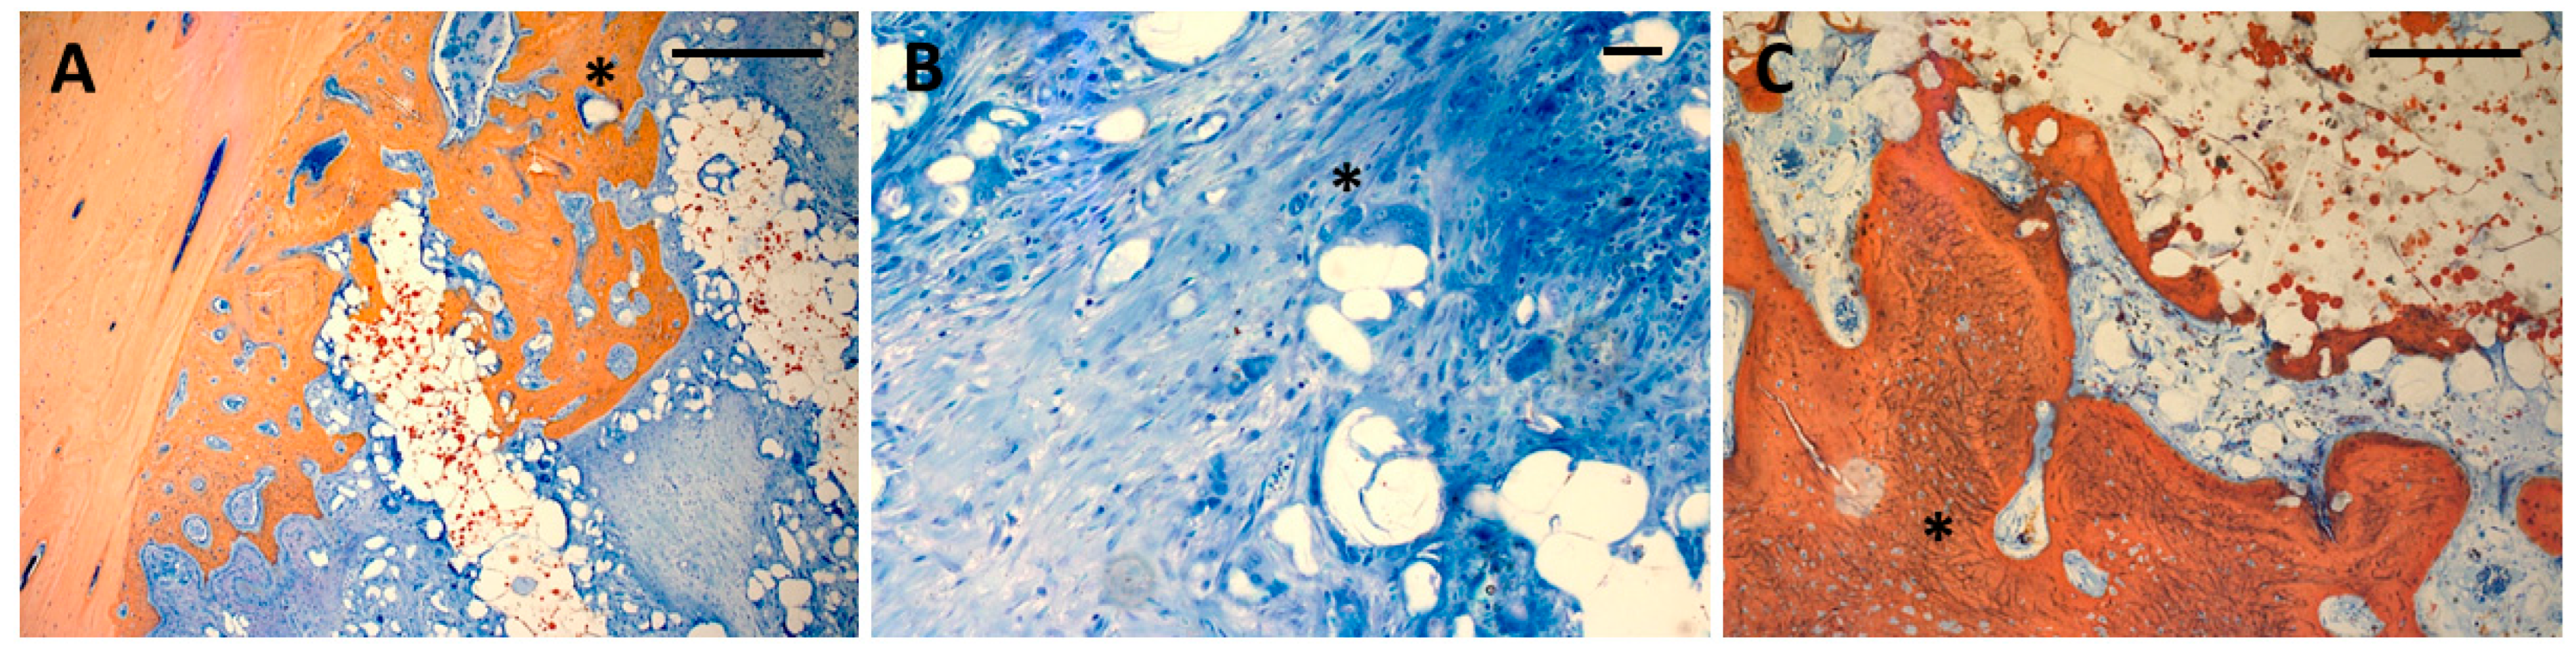

3.1. Histology

- Surface staining for histomorphometric assessment of bone formation using Alizarine red/Methylene Blue and van Gieson stains.